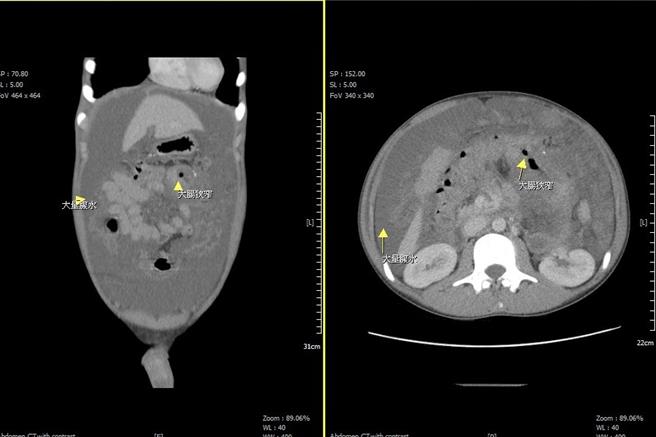

在电脑断层检查下发现大量腹水及大肠狭窄。(大千医院提供/谢明俊苗栗传真)

苗栗一位15岁少年近几个月来持续性腹胀不适、身体虚弱、体力下滑,日前更因腹胀不舒服前来苗栗县大千医院急诊就医,经外科部主任冯启彦检查发现,少年有严重贫血及大量腹水的现象,抽血检验癌症指数CEA竟高达16(正常值小于5)。进一步安排电脑断层穿刺及大肠镜切片之后,赫然发现少年竟然是大肠癌第四期,且癌细胞已在腹腔内扩散。